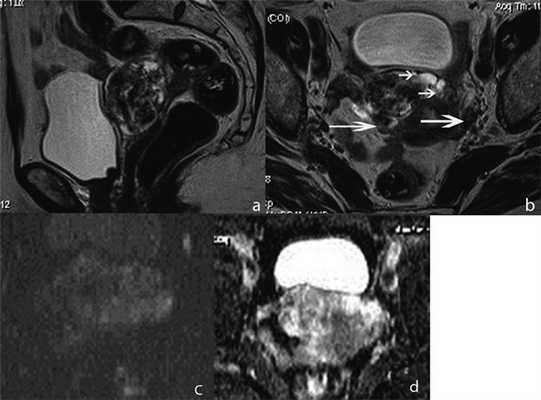

На МР-изображениях справа по передней стенке определялось интрамурально-субсерозное образование размером до 4 см, имеющее четкие дольчатые контуры с предполагаемым наличием псевдокапсулы (рис. 2); опухоль не распространялась на шейку матки и не демонстрировала связи с цервикальным каналом и полостью матки. Структура опухоли представлялась гетерогенной за счет кистозных включений и множественных расширенных сосудов, визуализируемых в виде характерных линейных участков пустоты потока; строма образования демонстрировала преимущественно гипоинтенсивный сигнал на Т2-ВИ, изоинтенсивный на Т1-ВИ с высоким показателем ИКД , на основании чего образование было охарактеризовано как лейомиома со сложной дегенерацией стромы. Обращало на себя внимание диффузное расширение сосудистых сплетений в миометрии передней стенки тела матки вокруг опухоли, а также в параметриях с высоким сигналом на Т2-ВИ spin echo, отражающим относительно низкие скоростные показатели кровотока, что было интерпретировано как возможное наличие сопутствующей сосудистой мальформации. В остальном в зоне исследования изменений выявлено не было.

Рисунок 2. МР-томограммы органов малого таза пациентки Х. Т2-ВИ в сагиттальной (а) и косо-аксиальной (б) плоскости;

ДВИ с b-фактором 800 с/мм 2 (в) и карта ИКД (г) в аксиальной плоскости. Опухоль характеризуется негомогенной структурой

с преимущественно низким сигналом на Т2-ВИ, имеет псевдокапсулу. Отмечается расширение сосудов в миометрии вокруг опухоли

(короткие стрелки), а также в параметриях (длинные стрелки). Показатель ИКД 1,57×10 -3 мм 2 /с.